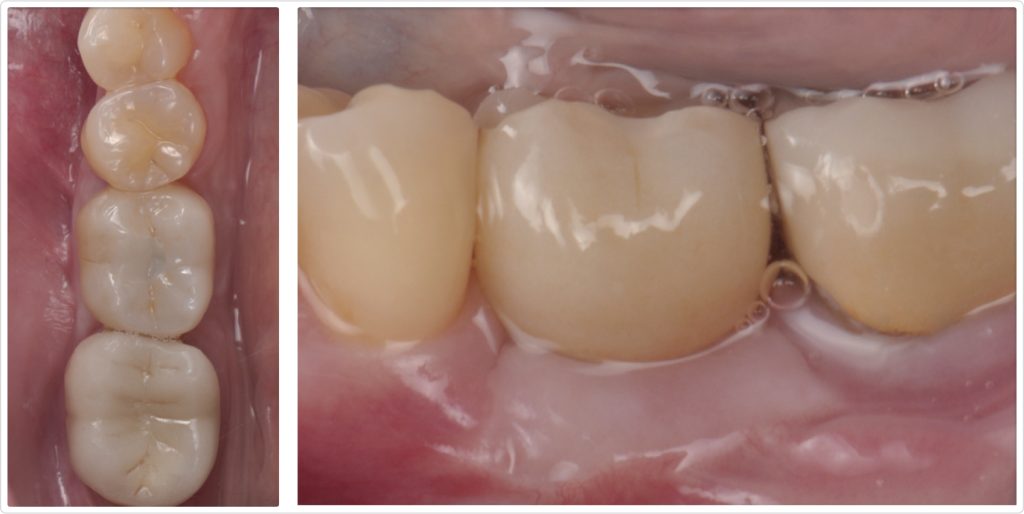

Six months after graft placement, the clinical pictures showed a well-integrated, screw-retained crown with more than 4 mm of keratinized tissue in both occlusal (Fig. 12a) and lateral (Fig. 12b) views. The presence of adequate keratinized mucosa provided a stable and healthy peri-implant environment, which is critical for the long-term success of the implant restoration.

A radiograph taken one year after crown delivery (Fig. 13) demonstrated stable marginal bone levels around the implant, confirming the success of the comprehensive surgical approach and the stability of the peri-implant tissues. This radiographic evidence was corroborated by clinical observations, which showed no signs of inflammation or mucosal dehiscence around the implant site. The stability of the bone levels indicated successful osseointegration, a critical factor for the long-term durability and functionality of the implant.

Furthermore, the clinical examination revealed a healthy mucosal contour with an adequate band of keratinized mucosa surrounding the implant. The presence of this keratinized tissue contributed to the overall health of the peri-implant tissues by providing a robust barrier against bacterial invasion and mechanical stress. The patient reported high satisfaction with the esthetic and functional results, noting an improvement in her ability to chew and a significant boost in confidence because of the enhanced appearance of her smile.